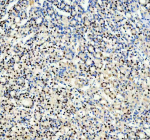

Immunohistochemical staining of SRARP using anti-SRARP antibody. SRARP was detected in a paraffin-embedded section of human bladder cancer tissue. Heat mediated antigen retrieval was performed in EDTA buffer (pH 8.0, epitope retrieval solution). The tissue section was blocked with 10% goat serum. The tissue section was then incubated with 2 ug/ml rabbit anti-SRARP antibody overnight at 4oC. Peroxidase Conjugated Goat Anti-rabbit IgG was used as secondary antibody and incubated for 30 minutes at 37oC. The tissue section was developed using an HRP secondary and DAB substrate.